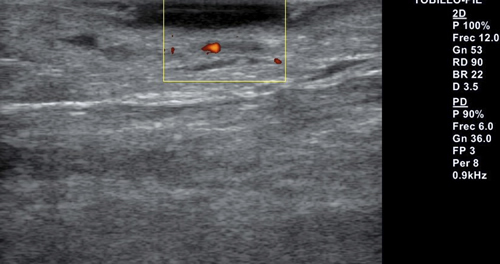

Se realiza exploración ecográfica vascular empleando para ello un equipo Alpinion E-cube 7 con una sonda lineal de 3-12 mHz, con una frecuencia de 12 mHz en la que destaca insuficiencia venosa y onda trifásica en arterias pedia y tibial posterior. Se realiza ecografía transulcerosa (Figura 2) mostrando área anecoica con punteado hiperecoico en su interior y con leve refuerzo acústico posterior, que afecta a la totalidad de la epidermis y penetra en dermis. Lesión bien delimitada, con ausencia de doppler en el interior de esta (Figura 3). Presenta una extensión ecográfica de 14 x 3.4 mm.

Figura 3. Ecografía transulcerosa con ausencia de doppler en el interior de la lesión.

Por otra parte, la ecografía se ha demostrado como un método eficaz para la evaluación de la lesión, dado que es una técnica poco invasiva, aportando gran información a tiempo real acerca de tamaño y delimitación de la lesión(6). Al aportarnos una estimación de su dimensión nos permitirá mejorar los márgenes quirúrgicos y darnos una visión más global de la lesión(11). En la ecografía podemos observar los CBC como una lesión sólida de patrón hipoecoico, con bordes irregulares, pero bien definidos, que suele localizarse en la unión dermo-epidérmica; como característica propia del carcinoma basocelular, la lesión cuenta con puntos hiperecoicos intralesionales que no suelen tener refuerzo acústico posterior. El estudio doppler de las lesiones no suele mostrar una alta vascularización(6,8).